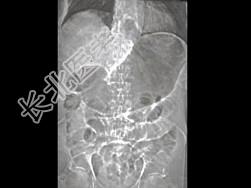

- 单项选择题急腹症患者,结合图像, 最可能的诊断为 ( )

A、结肠积气症

B、胃幽门梗阻

C、气肿性胃炎

D、胃癌

E、以上都不是